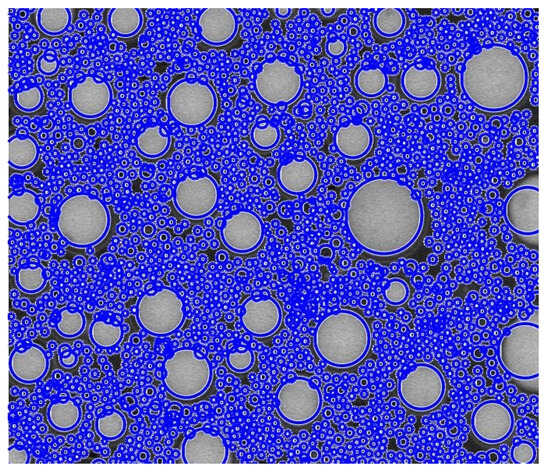

Biomechanical Comparison of Three Fixation Constructs for Tile Type C1.2 Pelvic Ring Fractures: A Finite Element Analysis

by Adrian Claudiu Carp, Bogdan Veliceasa, Dmour Awad, Alexandru Filip, Mihaela Perțea, Norin Forna, Bogdan Puha, Ștefan Dragoș Tîrnovanu, Mihnea Theodor Sîrbu, Silviu Dumitru Pavăl and Paul Dan Sîrbu

Life 2026, 16(2), 336; https://doi.org/10.3390/life16020336 - 15 Feb 2026

Fractures of the pelvic ring are among the most severe injuries in orthopaedic practice and Tile type C lesions are characterized by complete disruption of the posterior arch with both vertical and rotational instability. The optimal construct for posterior ring fixation remains a matter of debate. The aim of this study was to compare, by means of finite element analysis, the biomechanical performance of three different methods of osteosynthesis for Tile type C1.2 pelvic ring fractures: a transiliac plate, one iliosacral screw and two anterior reconstruction plates on the sacroiliac joint. A three-dimensional model of an intact pelvis was reconstructed from computed tomography images of a healthy adult male. A Tile type C1.2 injury pattern was created virtually, and three fixation constructs were designed in Ansys SpaceClaim according to manufacturer specifications. All materials were assumed to be homogeneous, isotropic and linearly elastic. Vertical loads of 400 N and 800 N were applied to the sacral endplate to simulate partial and full weight bearing, while the acetabular regions were constrained to represent standing stance. In this study, mechanical stability was operationally defined as resistance to global displacement under applied vertical load, with lower displacement indicating higher construct stiffness. Construct stiffness, total deformation and von Mises stress were assessed for bone and implants. For both loading conditions, the iliosacral screw construct showed the lowest overall displacement and provided the greatest stiffness. The transiliac plate construct presented larger displacements, whereas the anterior reconstruction plate construct provided intermediate stability with higher stresses at the sacroiliac joint. Among the analyzed constructs, the iliosacral screw provided the greatest stiffness and lowest overall displacement, suggesting superior mechanical performance under vertical loading conditions. Full article

Show Figures

Figure 1